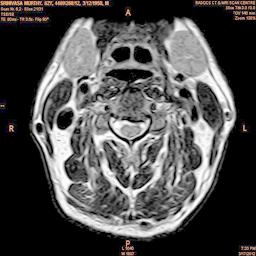

The proposed algorithm uses HSV color space to enhance spinal cord images since this color space offers many advantages such as color separation from intensity, reduced color distortion and efficient enhancement. The algorithm proposed takes advantage of this color space by performing enhancment operation on the intensity or value component and preserving the color information. The first column of Fig. 3 shows the original spinal cord test images followed by the extraction of value component presented in second column. Next, the third column of Fig. 3 shows the value component enhanced using the proposed multirate multiscale retinex algorithm. The modified version of the retinex algorithm presented here is capable of producing high quality reconstructed pictures, far better than the other researchers method.

The developed algorithm presented in the previous section was coded using Matlab Version 8.0. The experiment was conducted by considering poor quality spinal cord images of having various lesions. The first column of Fig. 4 shows the axial view of neck spinal cord images of size pixels, respectively. The second column of Fig. 4 presents the same images enhanced using histogram equalization. As is evident from the results presented, the histogram equalization method performs global image enhancement operation which improves the contrast of an image but at the cost loss in image details. The third column of Fig. 4 shows the MSR based spinal cord image enhancement. It can be seen that from the result presented, MSR scheme improves the details that are not clearly visible in histogram equalization technique. In general, image enhancement achieved by MSR method is better compared to histogram equalization. However, the MSR method voilates gray world assumption. Therefore, the image enhanced by this scheme appears to be grayish. Although, numerous work have been reported for solving the problem due to gray world voilation, no work seems to developed for complete elimination.

The fourth column of Fig. 4 shows the image enhanced using Chao et al. []. It can be seen from the results presented that the reconstructed images of Chao’s method have black spots. The appearance of these dark patches degrades the visual quality of the enhanced image. The image enhanced using proposed multirate multiscale retinex image enhancement method presented in the fifth column of Fig. 4, overcomes the drawback of the Chao’s method. As we can see from the simulation results, image enhancement achieved by the proposed method has improved details with significant contrast enhancement. The enhanced images from the proposed method provides information to physicians, radiologists and researchers for various types of pathology detection.